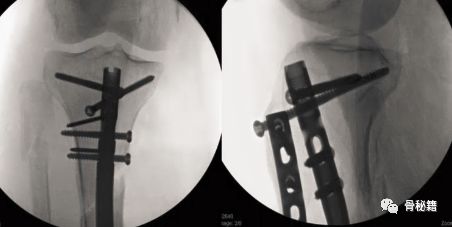

小钢板辅助复位,可以在胫骨棘前方行一个小切口,固定一个小钢板来辅助复位和维持复位,植入髓内钉后可取出也可不取。

该例骨折,移位较大,复位困难,可以先置放个小钢板

这样的骨折肯定长不上了,病人看了估计都会天天找你吧?翻修,近端加阻挡钉,小钢板